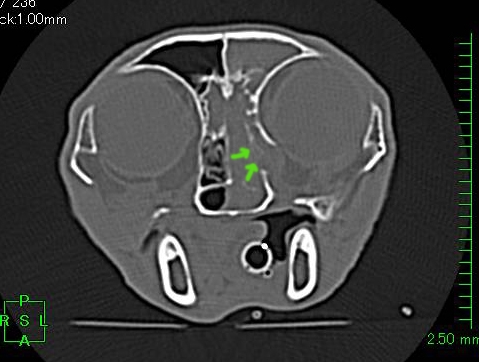

CT検査所見↓

眼窩骨を破壊する所見(矢印)